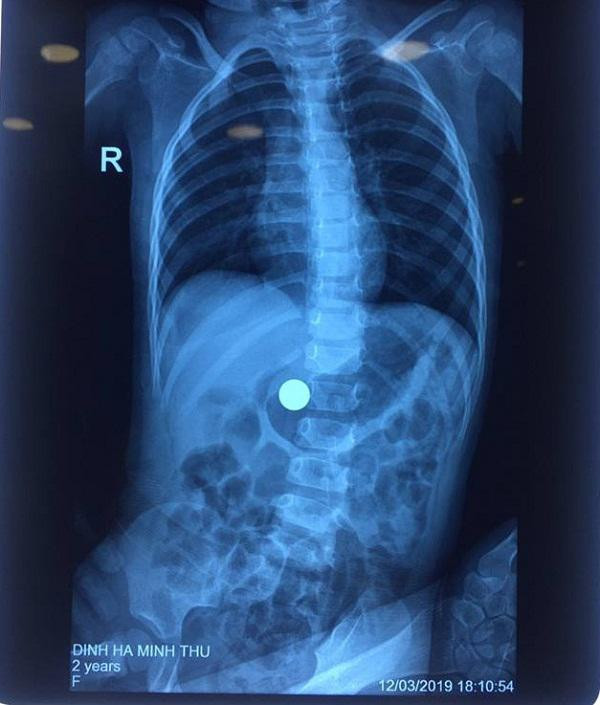

Tại bệnh viện, sau khi siêu âm và chụp X-quang các bác sĩ phát hiện vùng bụng của bệnh nhi có dị vật là viên bi sắt có kích thước lớn, nếu để lâu trong bụng bị thức ăn quấn quanh sẽ trở thành lõi, khối bã thức ăn lớn dần gây hẹp môn vị, có thể gây tắc ruột.

Vùng bụng của bệnh nhi có dị vật là viên bi sắt có kích thước lớn